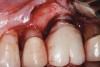

Achieving and maintaining healthy and stable peri-implant soft tissue requires the use of abutment materials that are biocompatible. This in part means using materials that have minimal affinity to bacterial colonization. Differences between titanium and zirconium abutments with regard to bacterial colonization have been of particular interest. Titanium- and zirconia-based surfaces are promptly colonized by bacterial communities similar to those found in adjacent teeth.9,16 Investigations have yielded differing results. A detailed quantitative analysis of an in vitro study found zirconia abutment surfaces have higher biofilm biomass and biofilm diversity than titanium surfaces.17 Figure 1 shows an example of an implant with a zirconia abutment with peri-implantitis.

Fig 1. Implant with zirconia abutment had peri-implantitis that led to gingival recession and exposure of the implant body.

Figure 1